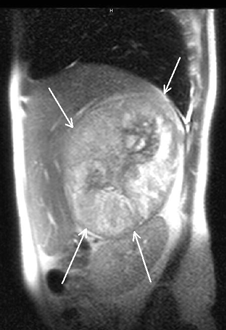

С начала 80-х гг. XX в. в клинической практике появился принципиально новый метод диагностики — МРТ, основанная на явлении ядерно-магнитного резонанса (рис. 7, 8, 9).

Рисунок 7. МРТ (горизонтальная проекция) — опухоль правого надпочечника

Рисунок 8. МРТ (сагиттальная проекция) — опухоль правого надпочечника

Рисунок 9. МРТ (фронтальная проекция) — опухоль правого надпочечника

Основные достоинства МРТ — неинвазивность, безвредность, трехмерный характер получения изображений. Однако этот метод является одним из самых дорогостоящих, и о применении МРТ при опухолях надпочечников существуют разноречивые мнения. По мнению Nakao Y.et al. (1993), МРТ перспективна для выявления опухолей малых размеров, а Н. Лавин (Эндокринология, 1999) считает, что МРТ в некоторых случаях дополняет результаты КТ, но при малых размерах опухоли надпочечника чувствительность этого метода не превышает чувствительности КТ. Однако, несмотря на использование различных инструментальных методов, точный диагноз, особенно при гормонально-неактивных опухолях, позволяет установить лишь морфологическое исследование, которое возможно при исследовании материала, полученного при аспирационной тонкоигольной биопсии под контролем УЗИ или КТ (Giron J., 1997; Petronio R., 1985) (рис. 10). Точность метода равняется 80–90% (Gonczi I. et al., 1987).